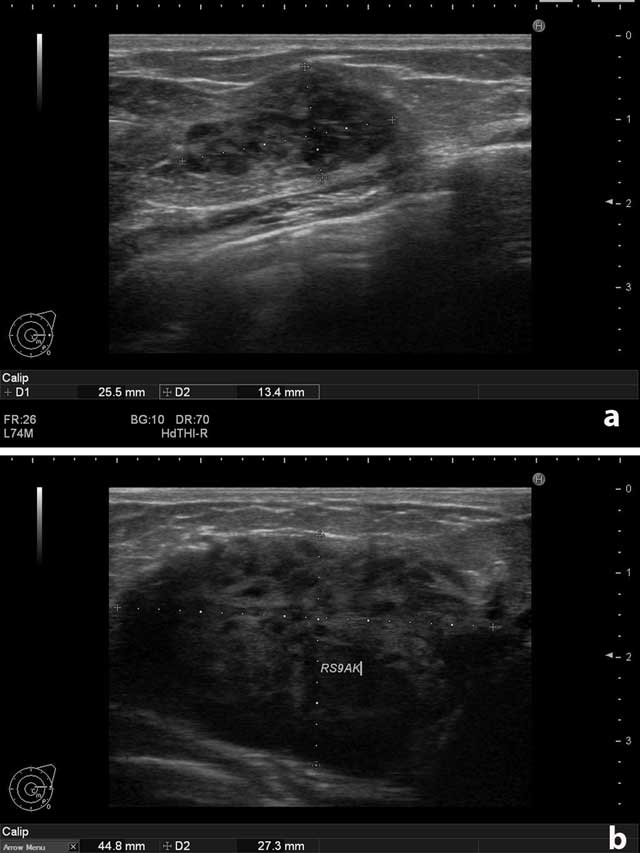

On physical examination, there were multiple palpable mass lesions in the lower quadrant in both breasts, with the largest being 4.5 cm in diameter in the right breast. There were no palpable axillary mass and no breast discharge or retraction of the areola. The ultrasonographic examination (Hitachi-Preius, 13–8 MHz) revealed multiple lobulated, hypoechoic, solid masses with circumscribed contours (Figure 1a). The largest mass measured 4.5 × 2.7 cm (Figure 1b). Power Doppler examination demonstrated increased vascularity in the masses (Figure 2a and b).

Figure 1

(a) Left breast. Solid, circumscribed mass. (b) Right breast. The largest solid mass measured 4.5 × 2.7 cm.